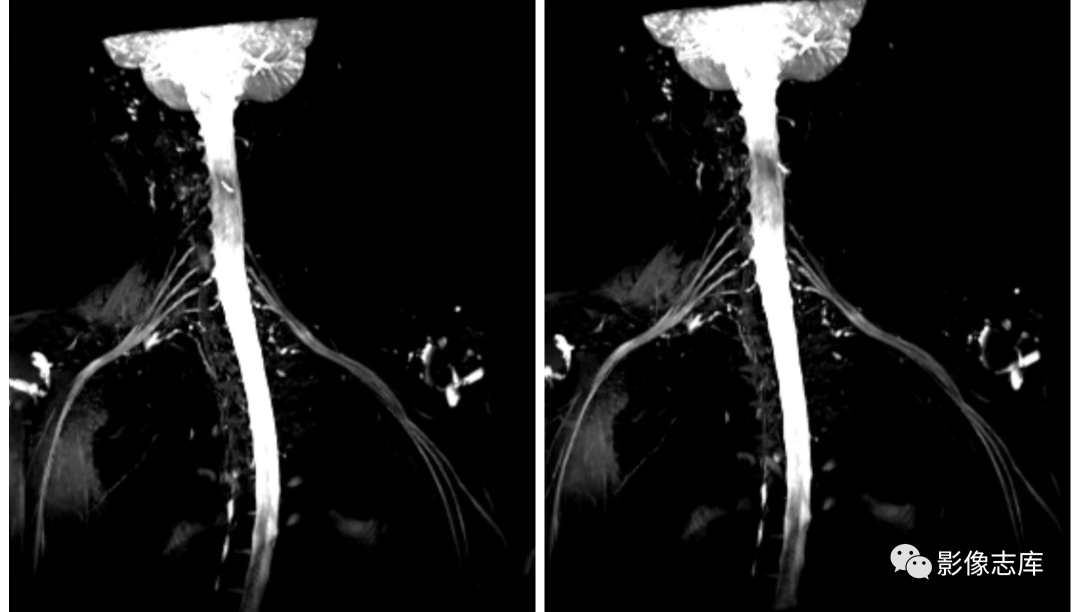

减轻模糊效应:SPACE序列在成像过程中使用了可变翻转角,大幅度增加回波链,减轻了T2衰减效应,避免了由于长回波链导致的模糊效应;

背景抑制:打药后进行T2 SPACE STIR cor 扫描,使背景抑制更彻底;

可实现各向同性:可进行3D等体素,扫描后可进行多方位重建,多角度观察臂丛神经;

高分辨:×450,明显提高图像空间分辨率;

虽然打药后可以很好的抑制背景,提高图像对比度,但是在成像过程中,还有一些疑问就是打药后多长时间扫描才能使对比剂正好流过成像区域内的微小血管和淋巴结,这样才能保证抑制的更加彻底,我们通常在打药后3分钟左右进行扫描,但是图像有时候还是不太理想。